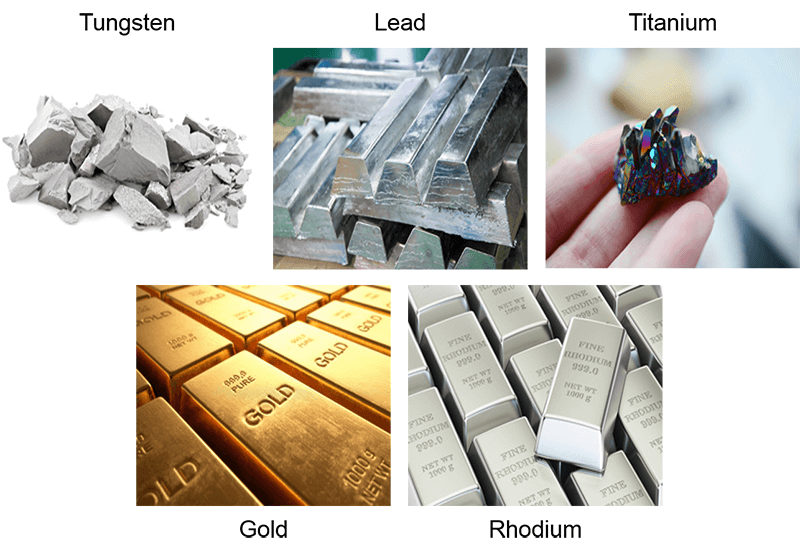

As mentioned earlier, the biggest problem with high-density metals is the artifact or image degradation that occurs on the resulting image. Most orthopedic devices such as artificial hips, artificial knees, pins, screws, etc are all made of these types of “MRI safe” metals, however, the images are not useful. In addition to the metals not creating a measurable signal, the surrounding signal is often distorted.

Contrary to what many people think, these metals will NOT be pulled out of the body or heat up, the MRI is just not diagnostic. Some piercings or other jewelry may be made of these metals. These types of items are removable for the scan and recommended. If the jewelry is within the coil, and in the area of interest, they will still create artifacts that may affect image quality. Some examples are tungsten, lead, titanium, and gold.